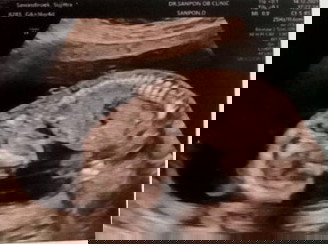

นัดตรวจดาวน์ซินโดรม

17 สัปดาห์กว่า วันจันทร์มีนัดตรวจท้องเสี่ยงดาวน์ เพราะแม่อายุเยอะ39ปี แถมท้อง3 แถมผ่าคลอดอีก คือตอนนี้เครียดหนักมาก หมอบอกว่ามดลูกบางมากๆ แม่เลือกตรวจที่รพ.รัฐ ตามสิทธิ์บัตรทอง แต่ฝากท้องคลีนิกนอก เลือดแม่ ตรวจพื้นฐานปกติดีทุกอย่าง ที่ผ่านมาท้องก็ผ่านมาด้วยดีตลอด วันจันทร์นี้จะเจออะไรบ้าง...เครียดมากๆเลยค่ะ แม่ๆท่านอื่น เจอปัญหาแบบนี้บ้างมั้ยค่ะ?!😩🥺😣